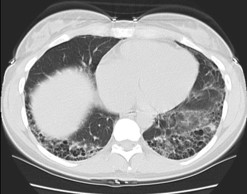

HRCTS ARE AN ESSENTIAL PIECE OF DIAGNOSING MANY ILDs

- HRCT creates high-resolution stacked X-ray slices to visualize internal organs27,28

- HRCT allows physicians to:3,29

- Differentiate features that help distinguish among various ILDs

- Assess progression of disease and to exclude concomitant processes such as emphysema, edema, or infection

PATIENTS WITH DYSPNEA AND/OR COUGH SHOULD HAVE AN HRCT TO LOOK FOR SIGNS OF ILD BECAUSE CHEST X-RAYS MAY APPEAR NORMAL30

Chest X-Ray

HRCT

Images courtesy of and used with permission from the American Thoracic Society.